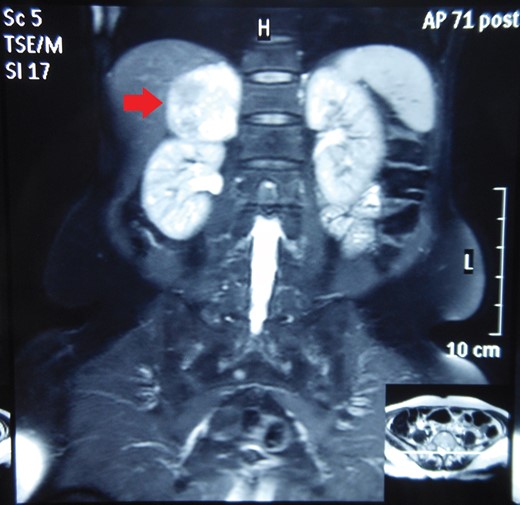

Routine laboratory tests were unremarkable. Ultrasound of the abdomen showed a 5 × 5 cm solid-cystic mass overlying the right kidney. CECT abdomen confirmed the presence of a right suprarenal tumour measuring 6 × 5 × 5 cm with solid-cystic components and fluid levels suggestive of intratumoural haemorrhage. Magnetic resonance imaging (MRI) of abdomen suggested an space occupying lesion in the right adrenal gland with multiple cystic spaces of variable sizes suggestive of pheochromocytoma. Fat planes to the adjacent structures were preserved with no evidence of metastases (Figs 1–4).

MRI abdomen showing a hyperintense right suprarenal mass (CORONAL SECTION).